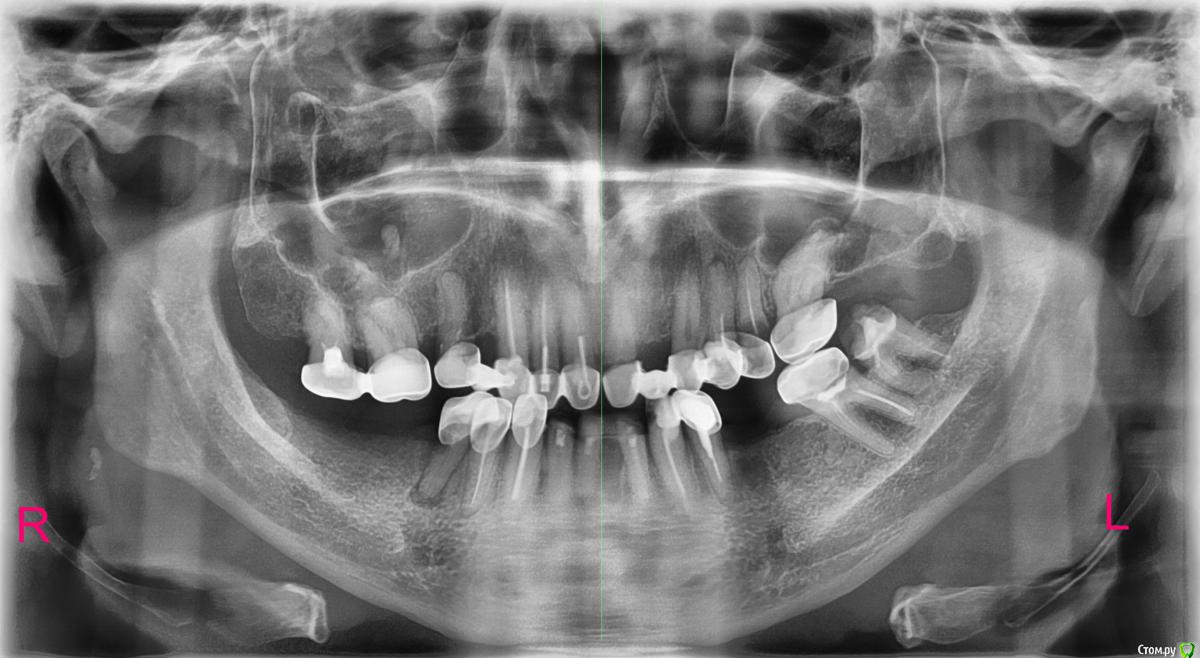

Surk Опубликовано 11 января, 2017 Поделиться Опубликовано 11 января, 2017 (изменено) Просьба помочь разобраться в следующей ситуации:Мне 45 лет. Сломалась коронковая часть на нижних резцах, обратился с просьбой о реставрации в районную поликлинику. Доктор не смогла пройти каналы. Как я понял из её беседы с другим врачом, дентикул в канале и корни (или каналы) тонкие. Вобщем, не пройдя канал, не получится сделать культевую вкладку, - не сделав культевую вкладку, не получится восстановить зубы. Предложили удаление и мост, с опорой на клыки. Я отказался и обратился в частную (платную) клинику. С трудом, но доктор смогла там пройти каналы (аккурат до апекса) и изготовить-установить вкладки и коронки. Попутно удалили левую-нижнюю еденицу (не в ряду распологалась). Короче, нижние резцы теперь в норме. Но доктор из частной клиники, узнав что я ношу свои штампованные коронки уже 9 лет предложила сделать ОПТГ (которое выкладываю). По результатам этого снимка теперь уже сделано следующее: сняты два больших моста на верхней челюсти справа 1-2-3-4-5 (4-отсутствующий зуб) и слева 1-2-3-4-5 (2-отсутствующий зуб) и пролечены (депульпированы) правый 5, левый 3. Перелечена 4 слева, также перелечены с культевой вкладкой 1 и 5 слева (5-ка пока в работе, под временной пломбой, там сильно разрушена коронка, под вопросом в общем - но надеюсь). На левой верхней 6 - также снята штампованая коронка и зуб (ранее леченый резорцин-формалином) перелечен с культевой вкладкой. На все упомянутые зубы одеты литые коронки ( фронтальные - вестибулярно покрыты керамикой). Также лечили дёсны (лазер, уколы линкомицин) - результат, ИМХО, прекрасный. Интересуют на данный момент правые 7 и 8 (6-отсутствует). Там продолжают стоять штампованные коронки, не протёрты, зубы эти не беспокоят. Нужно ли им что-нибудь делать ? Дело в том, что на данный момент кончились денежки (и до мая месяца точно не будет), а предстоит ещё разбираться с нижней челюстью (как минимум правый 5 и левый 8). Наверное согласился бы на имплантацию на нижней челюсти, да вот беда - курильщик (пачка сигарет на два дня примерно). На данный момент вместо моляров нижней челюсти работает бюгельный протез, который тоже нуждается в замене (если не импланты). Заранее благодарен всем, кто сможет высказать свое профессиональное мнение по поводу моей "тихой катастрофы"PS. прошу прощения за "много букв" - хотелось, по-возможности, подробнее... Изменено 11 января, 2017 пользователем Surk Ссылка на комментарий

Surk Опубликовано 26 января, 2017 Автор Поделиться Опубликовано 26 января, 2017 Сегодня был на приёме, лунка после удаления 25 зуба признана удовлетворительной. Заживает.Сделал новую ОПТГ, поскольку лечение верхней челюсти считается законченным. Хотелось бы знать ваше мнение о состоянии 17 и 18 зубов (они под штампованными старыми коронками и их не трогали), ну и в целом оцените качество лечения. Также буду благодарен за ценные замечания по поводу предстоящего лечения с последующим протезированием нижней челюсти.P.S. Доктору вполне доверяю, но как говорится, "доверьяй, но провэрьяй"Вот снимок: http://s020.radikal.ru/i706/1701/58/ddf2bae2ccef.jpg 1 Ссылка на комментарий